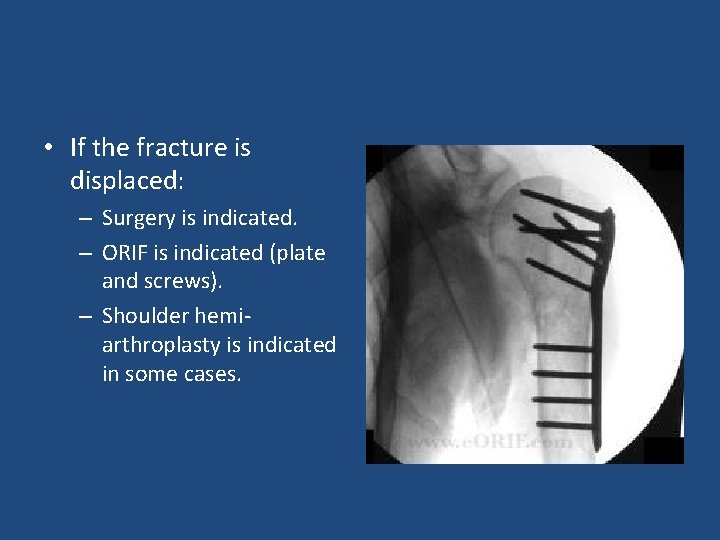

• If the fracture is displaced: – Surgery is indicated. – ORIF is indicated (plate and screws). – Shoulder hemiarthroplasty is indicated in some cases.